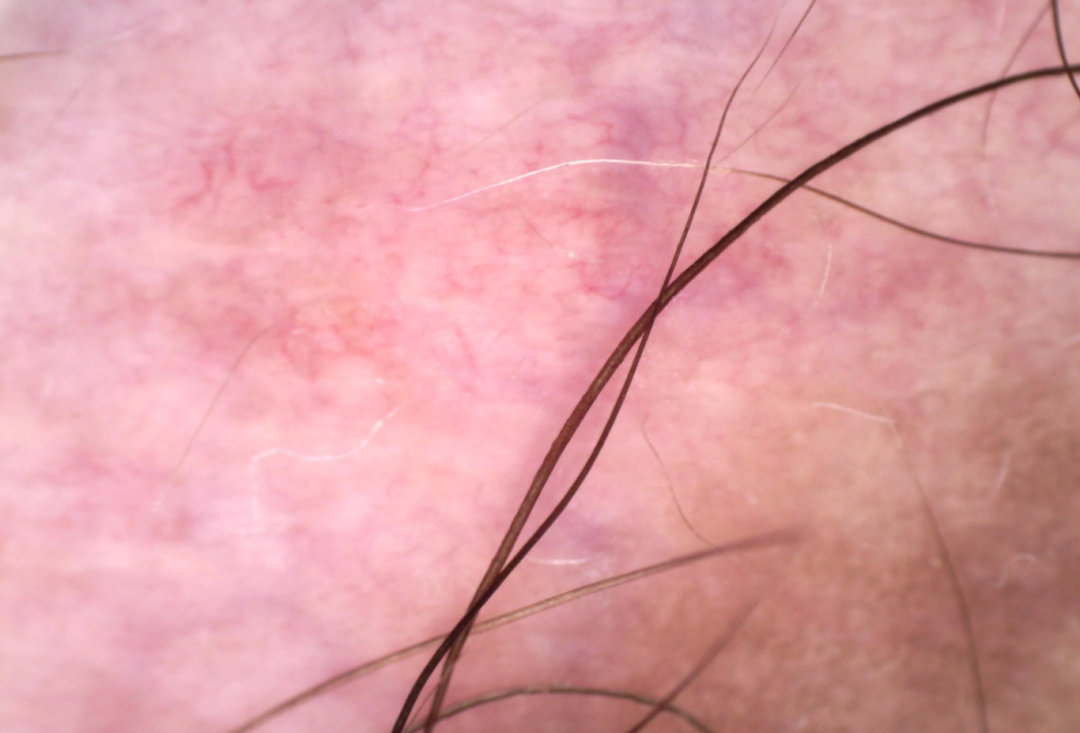

白癜风:进展期皮损边界模糊,核心特征是毛囊周围色素残留,常呈点状或环状分布,可伴有网状 / 星爆样色素分布、毛细血管扩张。稳定期白斑呈典型瓷白色,边界清晰,皮周色素加深形成沉着环,毛囊周围色素残留减少或消失。

老年性白斑:多见于 50 岁以上人群,表现为点状或圆形境界清晰的色素减退斑,白斑内可见点状、线状或不规则血管结构,表皮明显萎缩变薄。

无色素痣:先天性局限性白斑,呈苍白色,形态可呈锯齿状或不规则网状分布,部分伴有白发。白斑内可见线状、树枝状或网状血管,边缘与周围皮肤界限模糊,皮周无色素加深。

炎症后色素减退:有明确的原发病史(如湿疹、皮炎、外伤等),皮肤镜下色素减退斑边界模糊,形态与原发病皮损一致。常伴有毛细血管扩张、皮纹改变,无皮周色素沉着环。